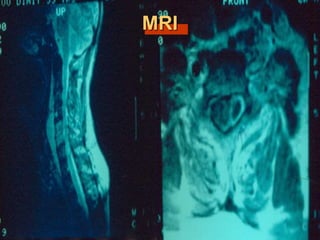

MRI

Spinal MRI is the procedure of choice

(sensitivity 95%, specificity 92%).

Gadolinium enhancement increases sensitivity

and enables better differentiation between

abscess and surrounding neurological

structures.